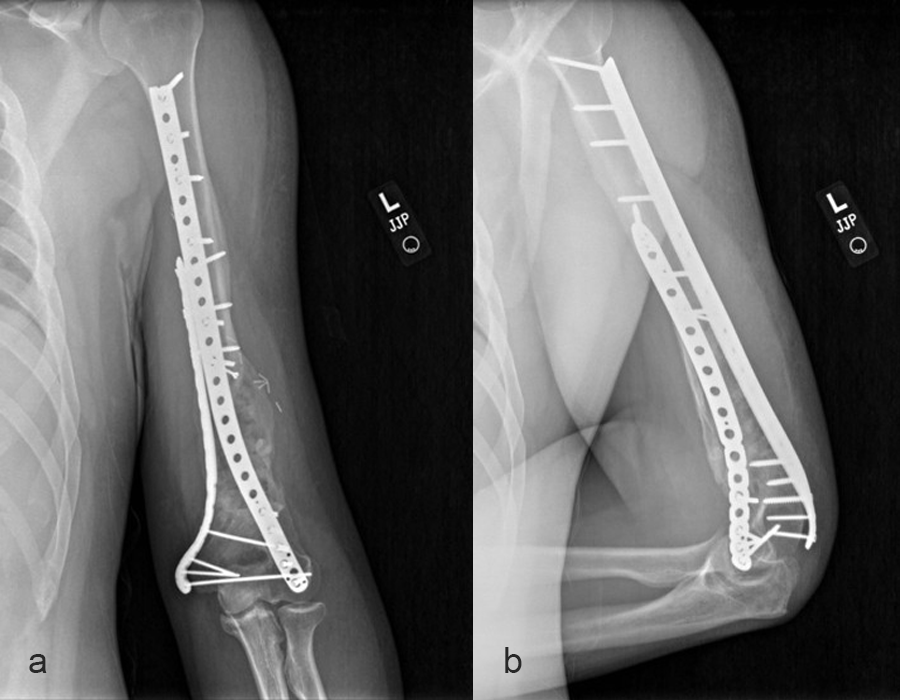

In a first stage, the distal humerus was debrided and devitalized bone was resected, leaving an 8cm defect into which a cement spacer was placed. New plates were inserted to stabilize the fracture (Fig 17 and Fig 18). Cultures taken in the OR were negative.

In October 2022, planning began for the second stage of surgery. A graft cage was planned (Fig 19) to allow the formation of new bone in the 8cm defect.

The second stage of surgery took place in October 2022. The cage was inserted (Figs 20-22) and filled with ~20cc autograft obtained by RIA of the femur, 30cc allograft and 3cc BMAC.